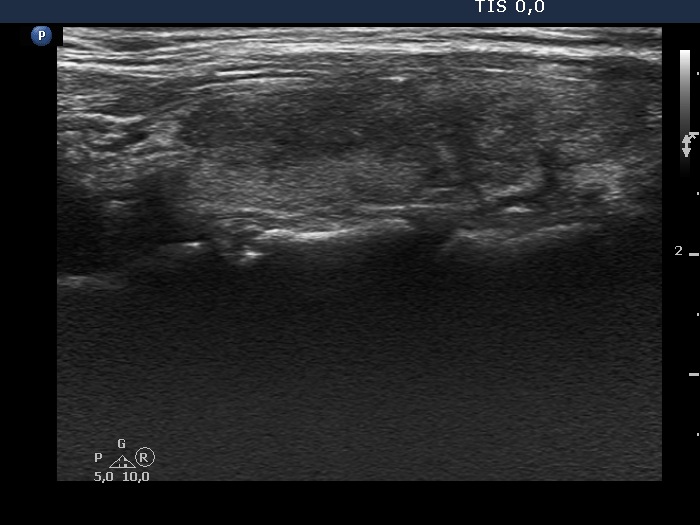

Right lobe, longitudinal scan

Right lobe, longitudinal view. In this section, more than half of the lobe is hypoechoic.